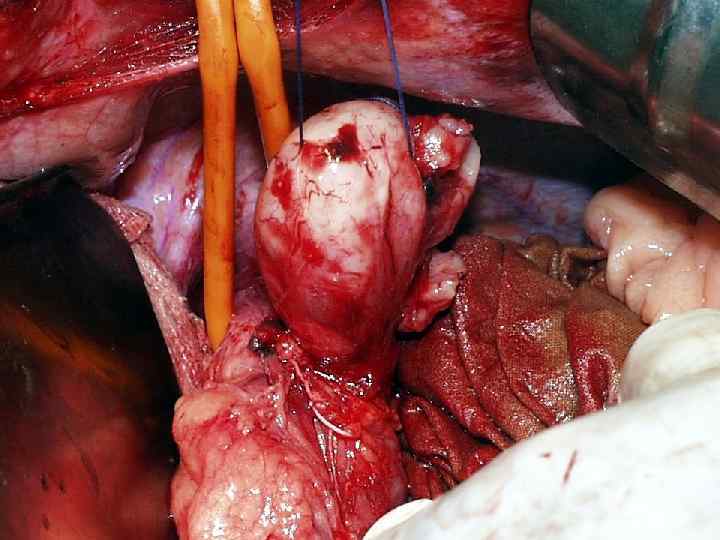

Больная Г. 33 г. Диагноз: гигантская лейомиома н/3 пищевода

Энуклеация лейомиомы

Больная Г. 33 г. Диагноз: гигантская лейомиома н/3 пищевода 18. 02. 2004 – энуклеация лейомимомы